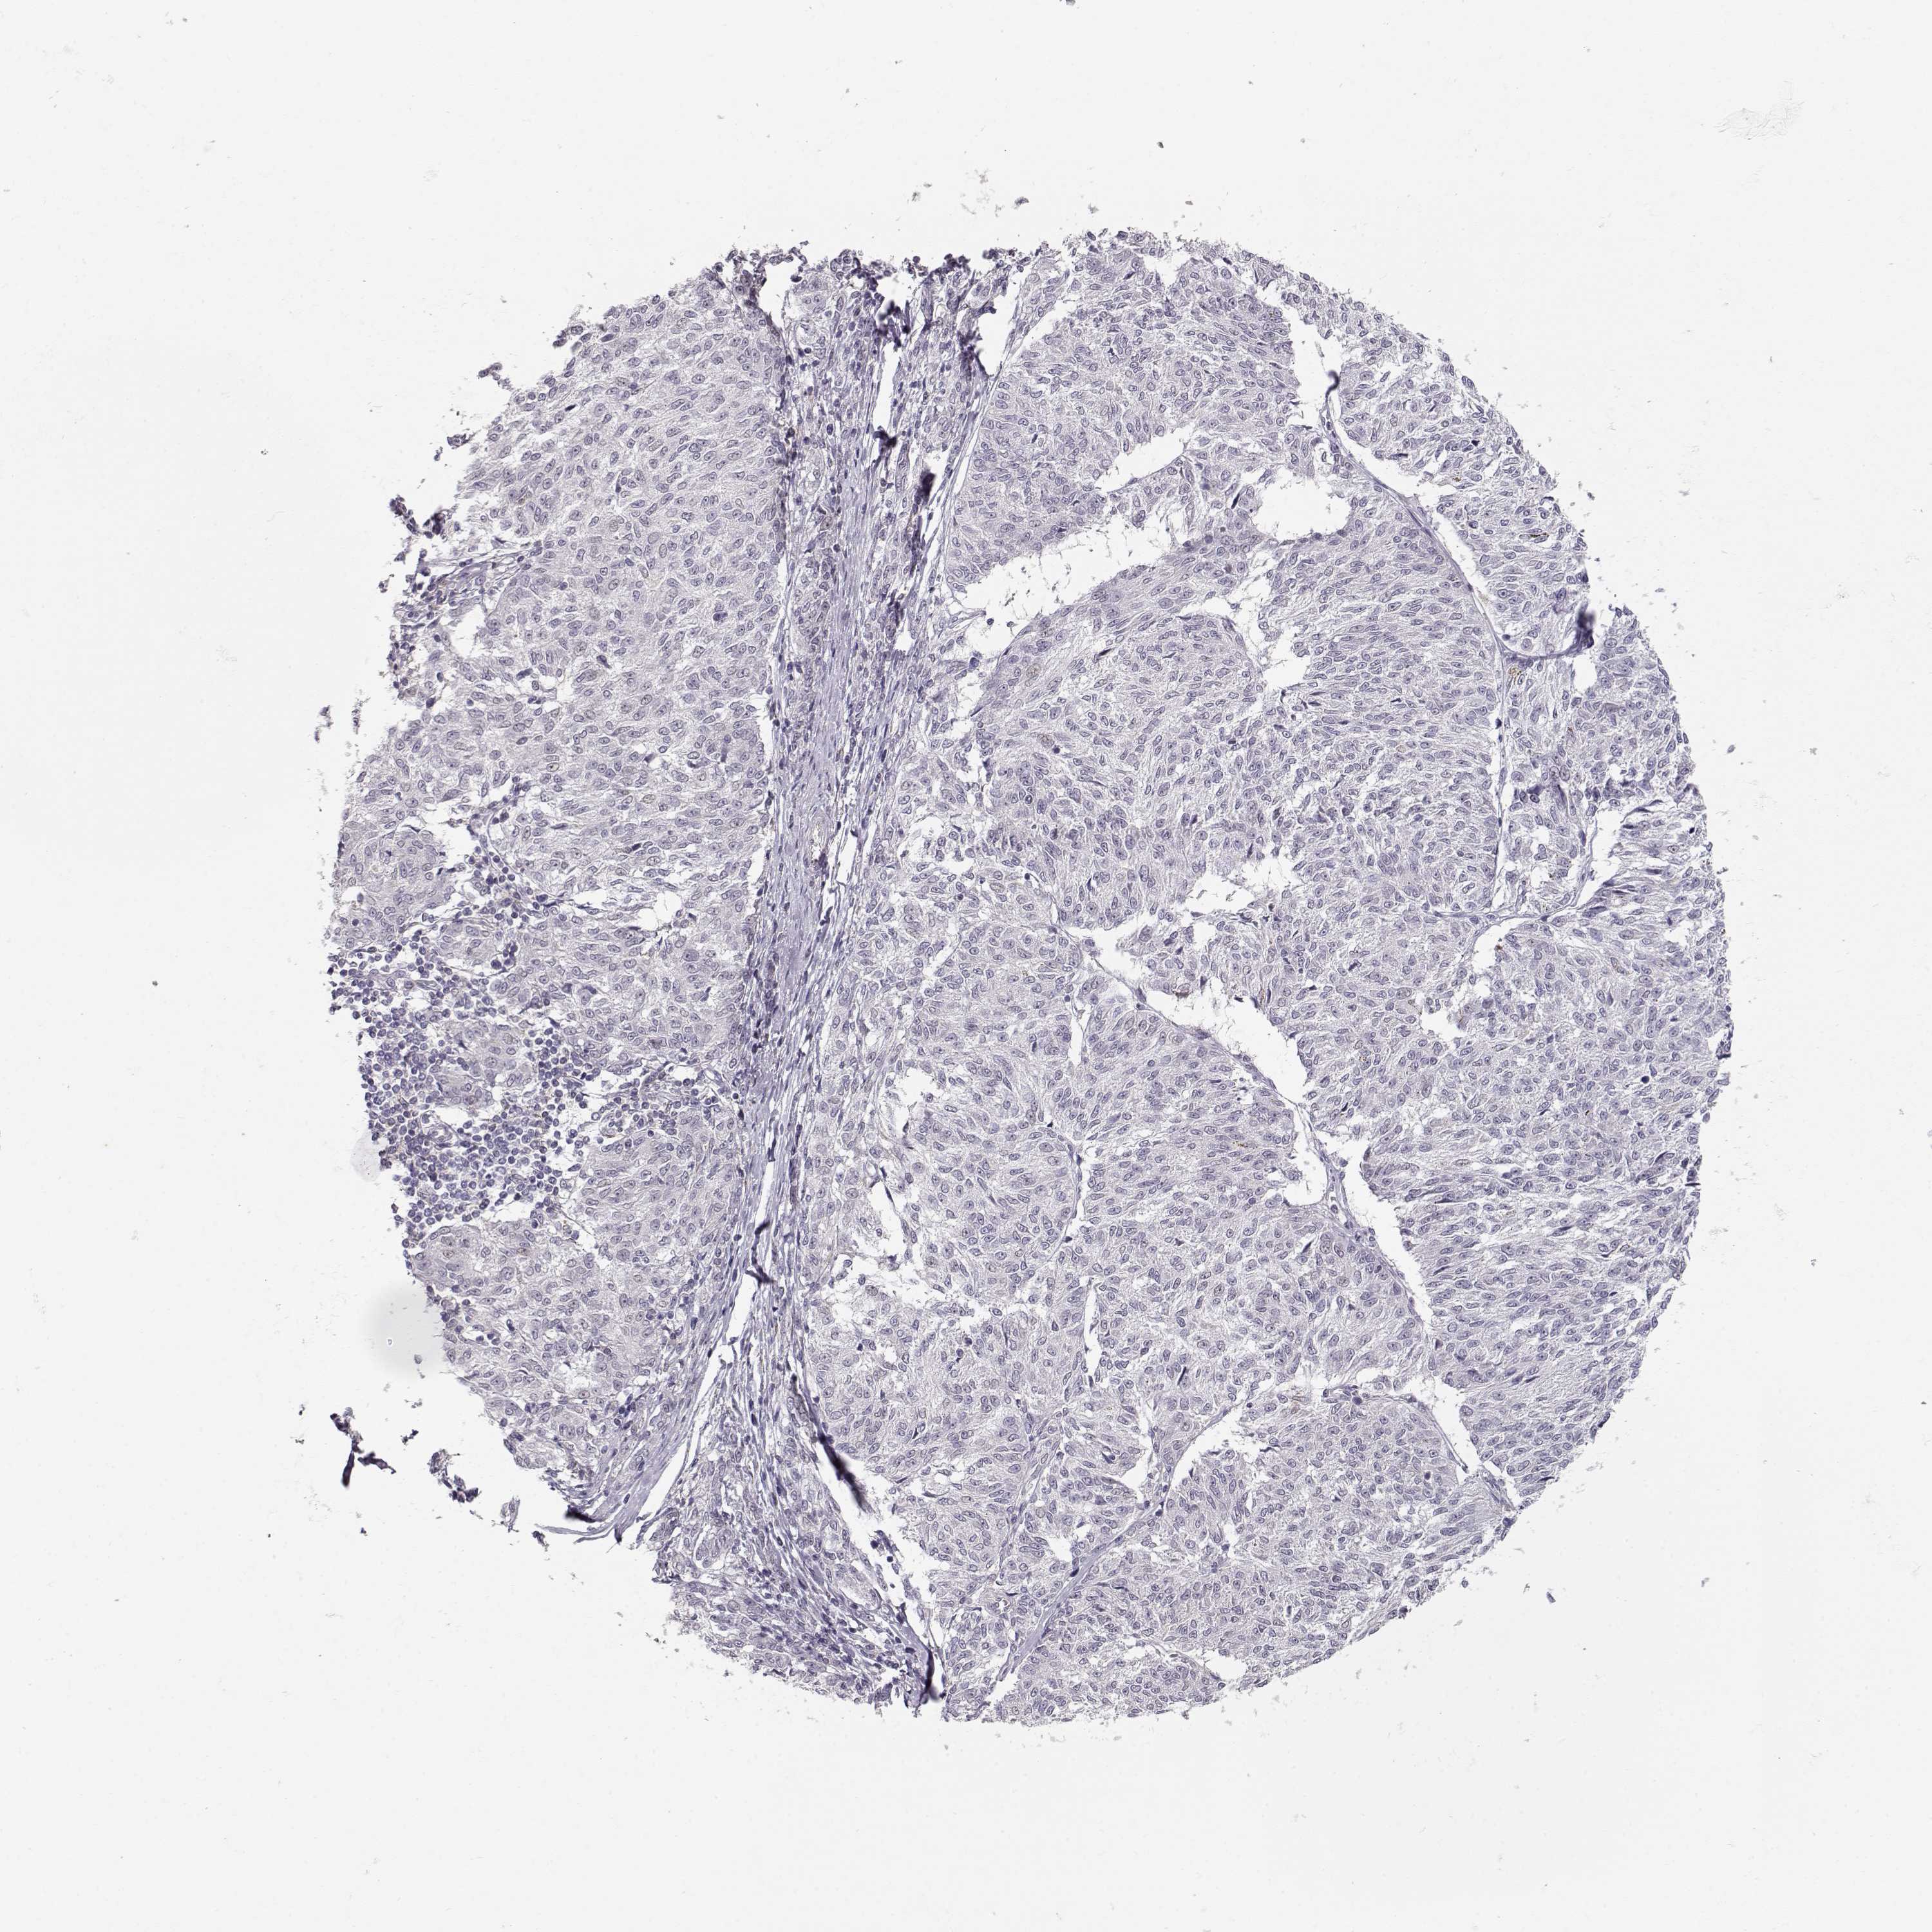

MELANOMA - Protein expressioni

A mouse-over function shows sample information and annotation data. Click on an image to view it in a full screen mode. Samples can be filtered based on level of antibody staining by selecting one or several of the following categories: high, medium, low and not detected. The assay and annotation is described here.

Note that samples used for immunohistochemistry by the Human Protein Atlas do not correspond to samples in the TCGA dataset.

Antibody stainingi

Antibody staining in the annotated cell types in the current human tissue is reported as not detected, low, medium, or high, based on conventional immunohistochemistry profiling in selected tissues. This score is based on the combination of the staining intensity and fraction of stained cells.

Each image is clickable and will lead to virtual microscopy that enables deeper exploration of all samples and also displays staining intensity scores, fraction scores and subcellular localization as well as patient and tissue information for each sample.

Antibody HPA062092

Staining

High

Medium

Low

Not detected

Intensity

Strong

Moderate

Weak

Negative

Quantity

>75%

75%-25%

<25%

None

Location

Nuclear

Cytoplasmic/membranous

Cytoplasmic/membranous,nuclear

Malignant melanoma, NOS

Malignant melanoma, Metastatic site